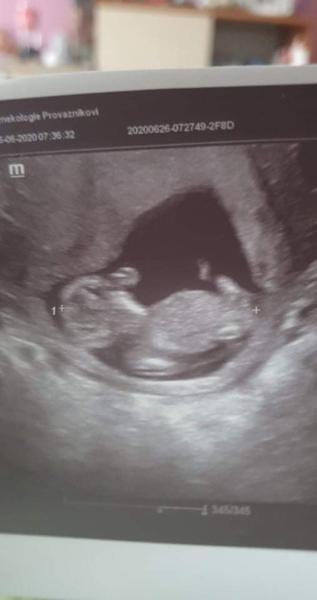

@ltaborikova Holcicka 😘. Nějak i podle tvaru hlavičky mi to připadá. Na druhou stranu já jsem mela taky podobnou fotku a byl to nakonec chlapeček. Ale bylo to brzy 12+0. Vy to mate o tyden pozdeji a tam by to mělo byt uz zřetelnější...